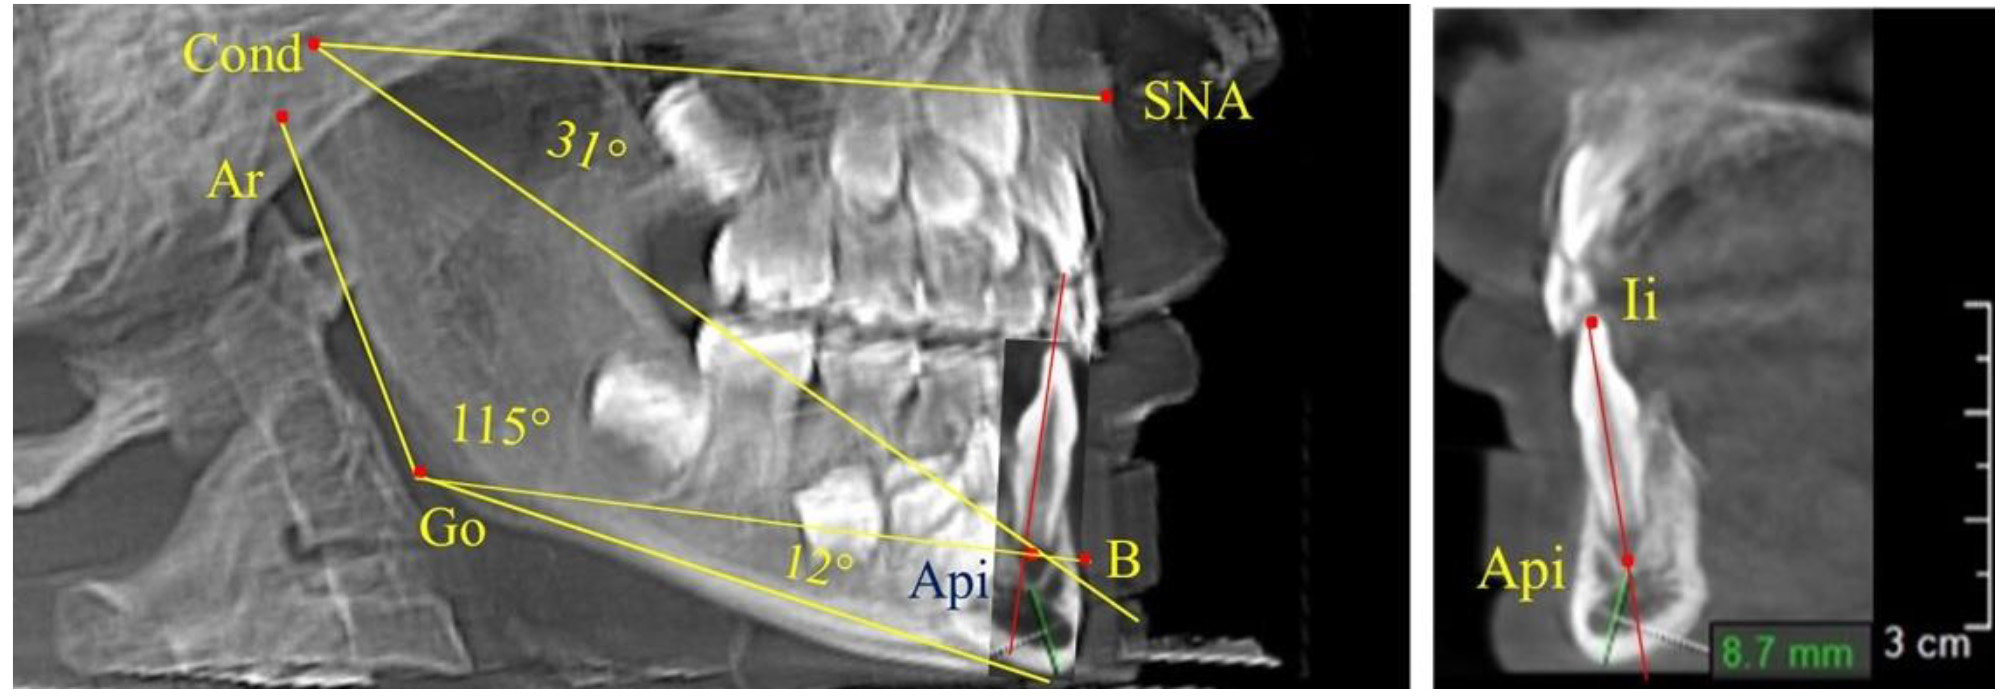

После смены всех молочных зубов (анализ 9 ТРГ) и после прорезывания вторых постоянных моляров (7 человек) происходил очередной этап подъема высоты прикуса с увеличением размеров костей гнатической части лица. Однако величина основного угла гнатической части лица SNA-Cond-Api, так же как в молочном и сменном прикусе, в норме составляла (30,02 ± 1,25)°, что не имело достоверных различий (р ˃ 0,05) с аналогичным параметром, анализируемом в других группах исследования. Угол нижней челюсти и его составляющие отличались вариабельностью параметров при различных показателях нижнечелюстного угла (рис. 6).

Рис. 6. Варианты 3D рентгенограмм детей после смены всех молочных зубов (а) и после прорезывания вторых моляров (б)

При анализе 16 рентгенограмм с аномалиями окклюзии в вертикальном направлении были выявлены признаки изменения основного гнатического угла. Так, для гнатических аномалий глубокой резцовой окклюзии/дизокклюзии (9 человек) отмечалось уменьшение угла гнатической части лица, величина которого была менее 26°. В то же время для гнатических аномалий (7 человек) вертикальной резцовой дизокклюзии («открытый» прикус) определялось увеличение угла гнатической части лица, который превышал значения в 33° (рис. 7).

Рис. 7. Варианты ТРГ при глубоком прикусе (а) и при открытом прикусе (б)

На представленных клинических примерах, несмотря на различия параметров основного угла гнатической части лица, определялись однотипные варианты угла нижней челюсти Ar-Go-Me и его составных частей Ar-Go-Api и Api-Go-Me.